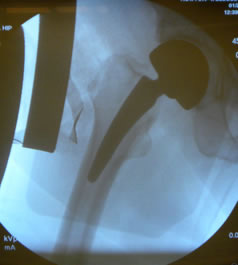

Post-op X-ray

As we have discussed many times slight varus stem positioning does not seem to make a clinical difference with neck stabilized stems.

Photos from His First Case